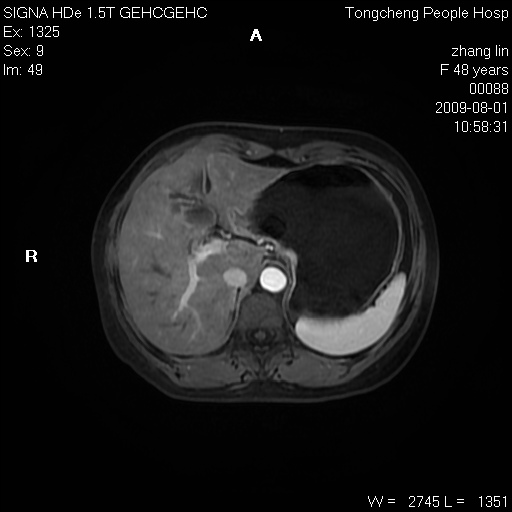

女,48岁。健康体检,彩超发现右肾占位性病变。平素健康。

临床诊断:右肾占位性病变,性质待定(囊肿?肿瘤?)。

上中腹部mr平扫+增强扫描,图像如下:

右肾上极见一类圆形病灶,t1wi呈等信号t2wi呈等高混杂信号,三期增强无强化,边界清---考虑囊肿出血。

同反相位均表现为等信号,病变无强化,考虑含蛋白的囊肿可能,弥散加权相或许有些帮助,

慢性胆囊炎